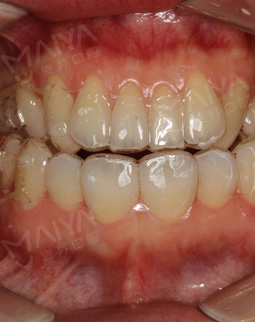

2018年4月 期盼了6年的牙套,真的非常精致

终于戴上了期盼6年的牙套,好美哦,忍不住发了朋友圈晒一下~好精致的牙套,医生说双膜的提速,是需要交替戴一下,所以第一周戴薄的,第二周戴厚的,看着小小的牙套,面对牙齿的时候就是展现它能量的时候了,材料都是很安全的~

第一次戴牙套没有任何不适感,医生亲自教佩戴,后来我只用了不到20秒,而且摘的时候也很方便,薄膜的牙套会比较软一些,医生讲的很细心,而且隐形的一点都看不出来,回家后宝宝也看不出来异样,很期待矫牙后的样子~